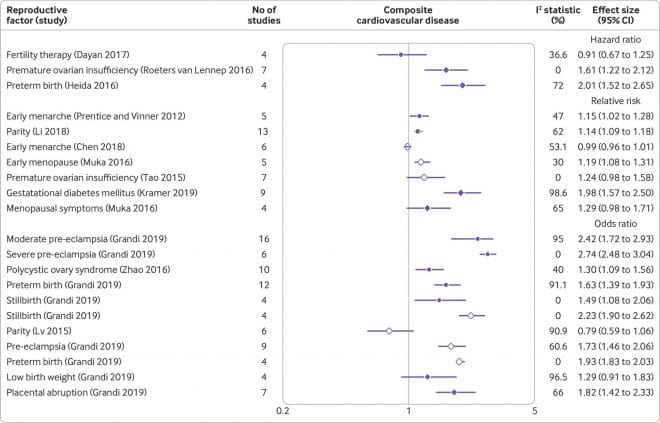

Οι ερευνητές του Πανεπιστημίου του Μπέρμιγχαμ, που έκαναν τη σχετική δημοσίευση στο βρετανικό ιατρικό περιοδικό «British Medical Journal» (BMJ), αξιολόγησαν όλες τις έως τώρα συστηματικές ανασκοπήσεις και μετα-αναλύσεις ερευνών (συνολικά 32) σχετικά με τη σχέση του αναπαραγωγικού «προφίλ» μιας γυναίκας και του καρδιαγγειακού κινδύνου της σε βάθος δεκαετίας.

Η νέα μελέτη-ομπρέλα συμπέρανε ότι αρκετοί παράγοντες κινδύνου και επιπλοκές (πρόωρη περίοδος ή/και εμμηνόπαυση, αντισυλληπτικά, αποβολή, θνησιγένεια, προεκλαμψία, διαβήτης κύησης, πρόωρος τοκετός, γέννηση λιποβαρούς μωρού) σχετίζονται με έως και διπλάσιο καρδιαγγειακό κίνδυνο για τη γυναίκα αργότερα. Ειδικότερα η προεκλαμψία τετραπλασιάζει τον κίνδυνο καρδιακής ανεπάρκειας.